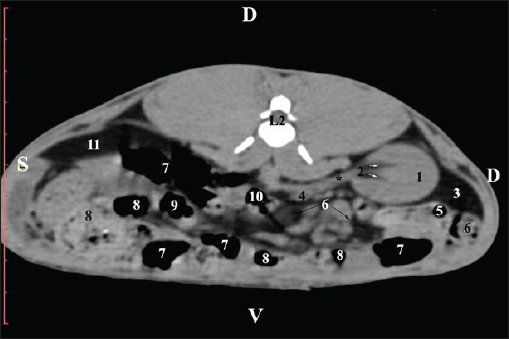

Fig. 1. Pre-contrast computed tomography (CT) anatomical scan of the regio abdominis cranialis at the Th13 level. (1) Lobus hepatis dexter; (2) ren dexter; (3) lobus caudatus (proc. caudatus) with visceral adipose tissue; (4) pars descendens of the duodenum; (5) ileum; (6) gl. adrenalis dextra; (7) colon ascendens; (8) cecum; (9) colon transversum; (10) colon descendens; (*) 13th rib. At the next scan level (L1), the normoattenuated image of the right kidney was more detailed and in contact with the lobus hepatis dexter, lobus caudatus, duodenal pars descendens, and ileum. The cortex renis and medulla renis were not clearly differentiated. Pelvis renalis appeared as a linear hypoattenuated finding against the relatively normoattenuated kidney cortex and medulla. The proximal part of the ureter was seen medial to the right kidney (Figs. 2 and 3).

Fig. 2. Pre-contrast computed tomography (CT) anatomical scan of the regio abdominis cranialis at the L1 level. (1) Ren dexter; (2) lobus hepatis dexter; (3) lobus caudatus (proc. caudatus) with visceral adipose tissue; (4) pars descendens of the duodenum; (5) ileum; (6) cecum; (7) colon ascendens; (8) colon transversum; (9) colon descendens; (10) jejunum.